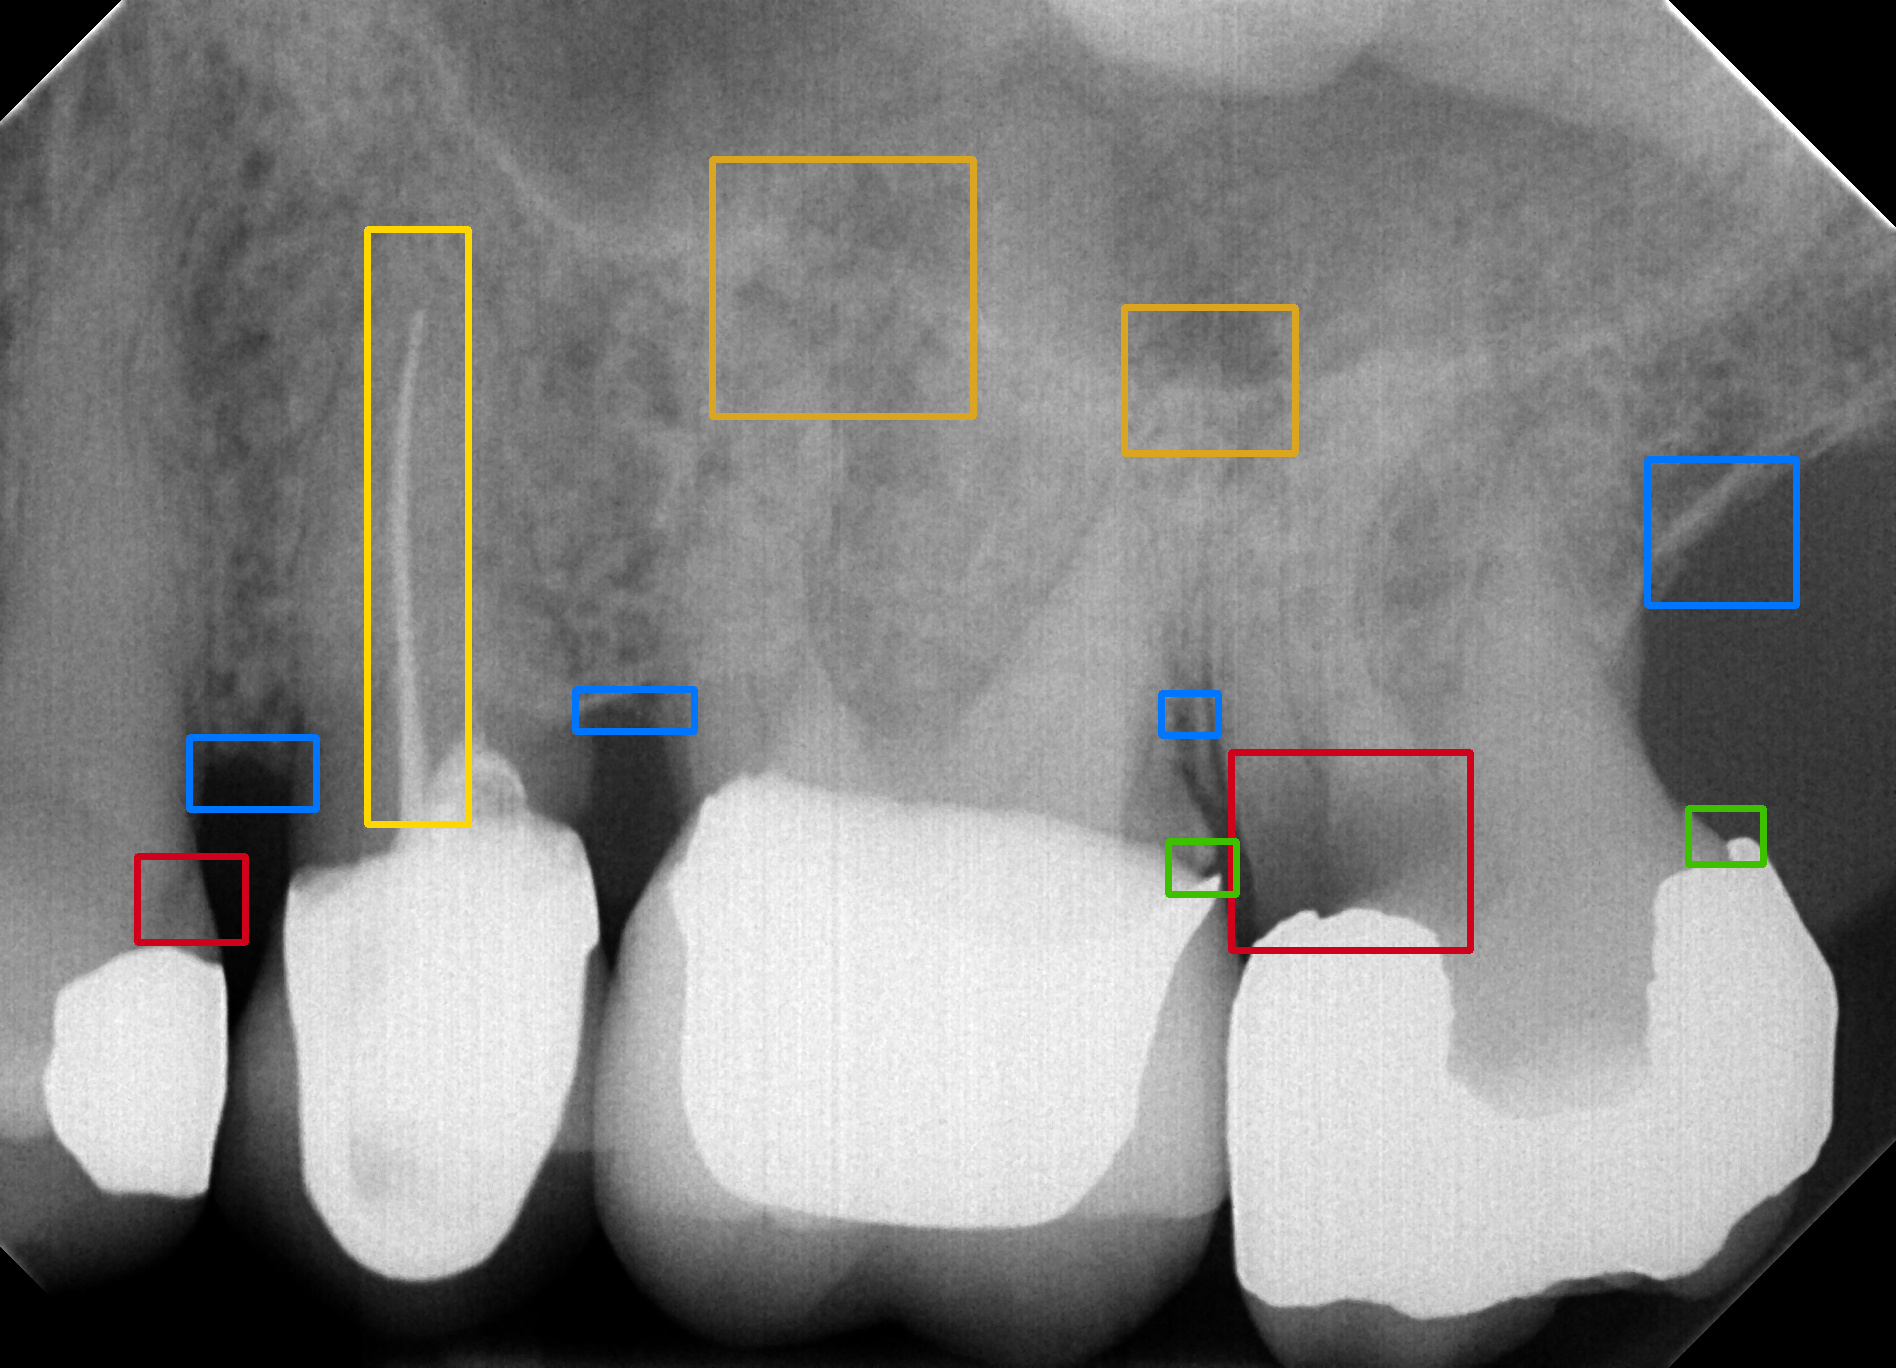

In the first part of the clinical study, called the control arm, a benchmark was set for the regular workflow of inspecting intraoral images. First of, the IOR images were randomly divided into disjunct subsets of (or in one case ) images. Seven new dentists (with either DDS or DMD qualifications and sufficient clinical practice) were asked to each analyze one of these subsets of unprocessed IOR images for the six anomaly categories listed in § 1. To facilitate and track the evaluation, these dentists manually annotated the original IOR images by drawing rectangular bounding boxes at the location of the various anomaly instances that they could distinguish. The annotations were made using the online image annotation tool Supervisely (https://supervise.ly). The bounding boxes for each anomaly type all have a predefined color. An example is shown in Fig. 1.

In the study portion of the clinical validation study, each of the seven dentists was shown the same series of (or ) images as in the control arm. In this case, the images were already analyzed beforehand by the AI-based anomaly detection algorithm. The anomaly locations predicted by the algorithm were also depicted on the IOR image using the setup with colored bounding boxes in the annotation tool. The dentists were asked to look for the six anomaly types in each IOR image in their respective image batch using the algorithmic output for guidance. In practice, the dentists could leave the annotating bounding boxes in place for the anomalies that they were in agreement with. Note that repositioning and resizing the boxes was also possible. Further, they were asked to remove all boxes for anomalies that they judged not to be there. Additionally, they could add boxes for anomalies that they considered to be undetected by the AI algorithm. The end results were stored as the algorithm-assisted annotated images. To avoid any recall bias, an idle period of 4 weeks was implemented in between the control and study phase. Also, we switched the order of the control and study phase for three randomly chosen dentists.